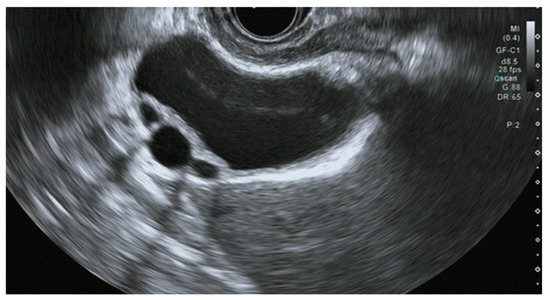

8.1. Differential Diagnosis of Wall Thickening Lesions

- Kim, H.J.; Park, J.H.; Park, D.I.; Cho, Y.K.; Sohn, C.I.; Jeon, W.K.; Kim, B.I.; Choi, S.H. Clinical usefulness of endoscopic ultrasonography in the differential diagnosis of gallbladder wall thickening. Dig. Dis. Sci. 2012, 57, 508–515. [Google Scholar] [CrossRef] [PubMed]

- Rana, P.; Gupta, P.; Kalage, D.; Soundararajan, R.; Kumar, M.P.; Dutta, U. Grayscale ultrasonography findings for characterization of gallbladder wall thickening in non-acute setting: A systematic review and meta-analysis. Expert. Rev. Gastroenterol. Hepatol. 2022, 16, 59–71. [Google Scholar] [CrossRef] [PubMed]